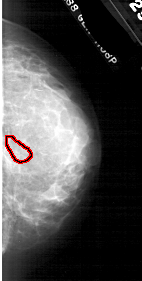

A_1746_1.RIGHT_CC

RIGHT_CC LINES 3931 PIXELS_PER_LINE 1981 BITS_PER_PIXEL 12 RESOLUTION 43.5 OVERLAY

FILE: A_1746_1.RIGHT_CC.OVERLAY

TOTAL_ABNORMALITIES 1

ABNORMALITY 1

LESION_TYPE CALCIFICATION TYPE PLEOMORPHIC DISTRIBUTION CLUSTERED

ASSESSMENT 4

SUBTLETY 1

PATHOLOGY BENIGN

TOTAL_OUTLINES 1

BOUNDARY